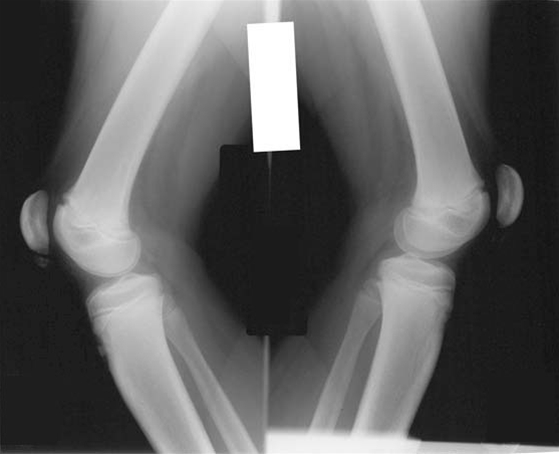

Radiologisk undersøgelse er ikke obligatorisk, hvis der er karakteristisk klinik, men bør udføres i differentialdiagnostisk øjemed ved atypiske klager og objektive fund.

• De radiologiske forandringer kan vise ossøs fragmentering

• Lateral projektioner kan vise forkalkninger nedenfor nedre pol af patella, i patellarsenen, såvel som bløddelshævelse over forkalkningerne. Forkalkningerne er almindeligvis inkorporeret i nedre pol af patella

• Disse fund indikerer Sinding-Larsen-Johanssons sygdom, men de kan dog være tilstede hos raske

• Patienter med Osgood-Schlatters sygdom kan have lignende røntgenfund, men de er lokaliserede til det distale fæste for patellasenen på forreste tuberositas tibia

• Ultralyd kan også demonstrere fragmentering af patellas nedre pol, patellar senefortykning og infrapatellar bursitis